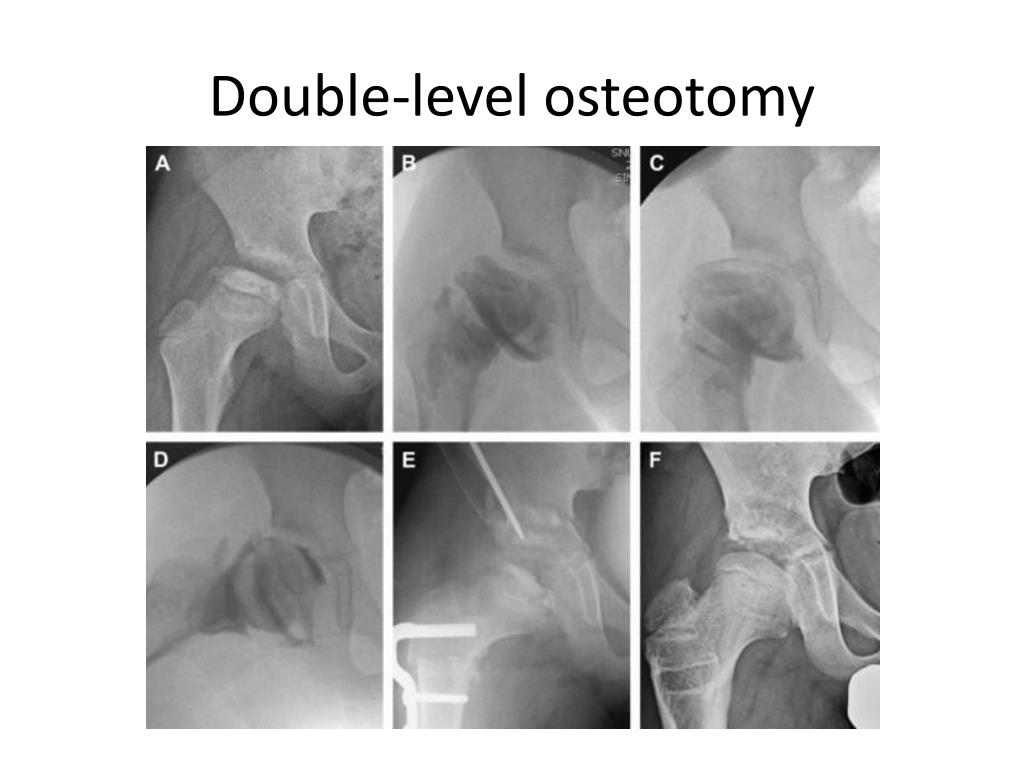

30. Double-level osteotomy